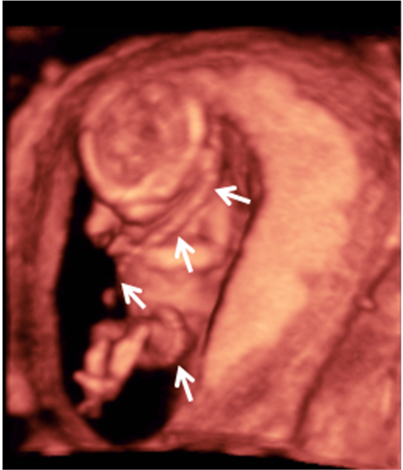

He aquí un signo inequívoco de bienestar fetal: los movimientos vigorosos de un bebé en su semana 12 de gestación. La ecografía 4D muestra al niño en movimiento, junto con la placenta y el cordón umbilical dentro de la cavidad uterina.

Ecografía en 4D de feto de 12 semanas en movimiento

La variedad de movimientos de este bebé de 12 semanas de gestación es muy amplia. Las imágenes muestran cómo cambia de postura varias veces y agita con energía brazos y piernas. Para los ginecólogos, los movimientos de la criatura indican vitalidad, son un signo positivo de salud fetal. En la ecografía en 4D (vídeo) se aprecian casi todas las estructuras externas de la criatura, además del cordón umbilical y la placenta (ambos conectados entre sí), en el margen superior izquierdo de la cavidad uterina.